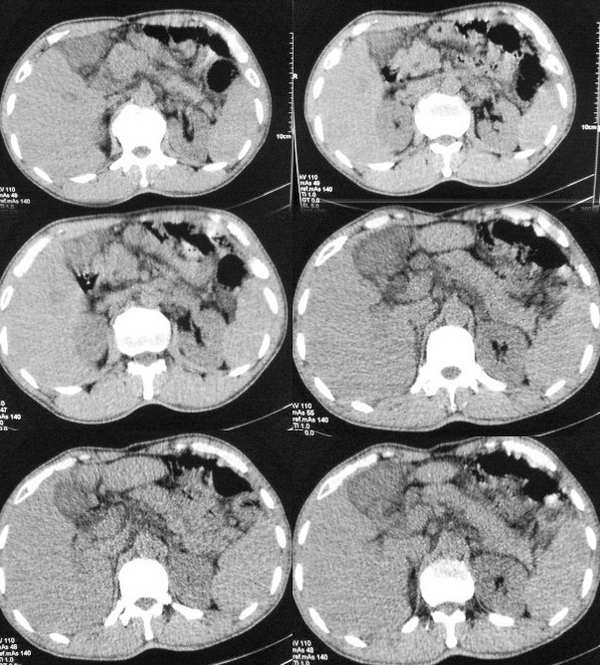

以下是引用butterylf在2005-12-21 19:10:00的发言:[br]我扫出来的图像都是这样的,窗宽窗位我参考了别的医院的啊,可是为什么我扫出来的图像质量不好,不好意思,是从显示器上拍的,而且还是用手机拍的,我不知道其他还能有什么方法拍啊!![br]病人是男性,41岁,[br]另外mas怎么调,不是不同的部位都要重新调过吧,?[br][br][br]对了,各位老师,我想问一个问题,我现在扫描片子打不出来了,这是为什么?ct已经传送过去了,可是激光打印就是出不来啊,打印机上总是显示close lower cover?这是为什么啊?